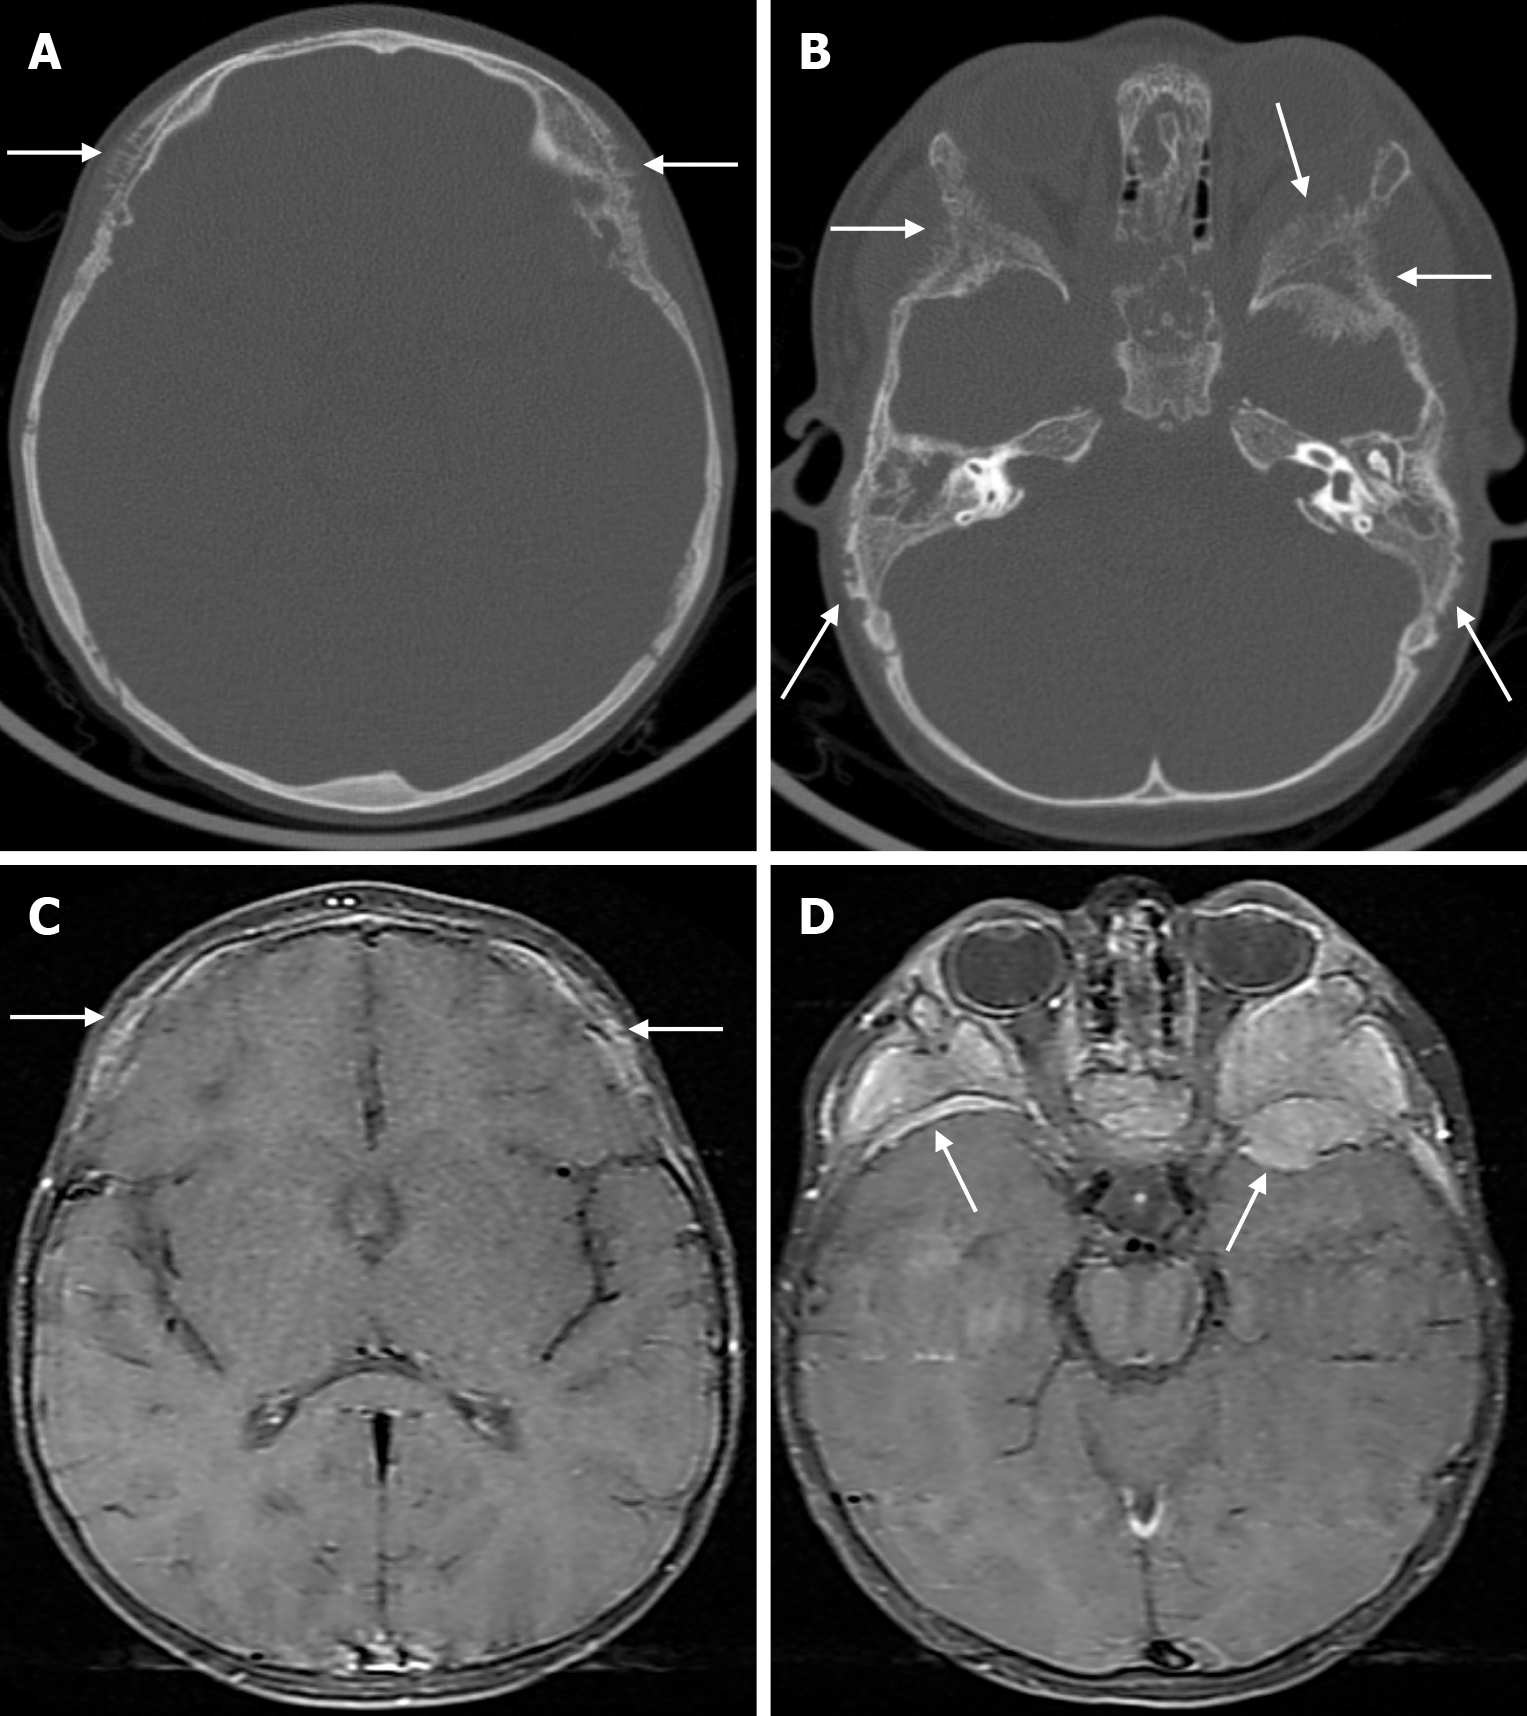

Skeletal changes in chronic anemia are due to ineffective erythropoiesis as a result of impaired haemoglobin synthesis, peripheral destruction of erythrocytes and consequently reduced erythrocyte lifespan. Radiography show massive hyperplasia of the bone marrow associated with hyperactivity of the bone marrow in response to anemia. The hair-on-end sign is seen on plain radiography of the skull, CT and MRI as long, thin vertical lines of calcified spicules perpendicular to the bone surface, appearing as upright hairs. The hair-on-end appearance of the skull is a characteristic feature of chronic haemolysis, usually seen in patients with thalassaemia (Figure 14) and sickle cell disease. The incidence of hair-on-end appearance in patients with thalassaemia is 8.3%. Although rare, the hair-on-end sign has also been described in iron deficiency anemia, sickle cell disease, cyanotic congenital heart disease, hematological malignancies and nutritional deficiencies. The appearance of these projections indicates excessive medullary erythropoiesis in patients and is rare before the age of 5 years. As the bone lesions are explained by the relationship between proliferating bone marrow and bone cortex, only hypertransfusion initiated early in life will prevent the development of the abnormality[55].

Renal osteodystrophy refers to abnormalities of bone morphology in chronic renal failure. Phosphate retention and reduced vitamin D conversion lead to hypocalcemia, which stimulates parathyroid hormone production and causes bone resorption. Therefore, factors such as secondary hyperparathyroidism and abnormal vitamin D metabolism contribute to renal osteodystrophy. Some imaging features of renal osteodystrophy overlap with those of hyperparathyroidism and rickets or osteomalacia. Skeletal findings in renal osteodystrophy include generalised demineralization, trabecular thickening, subperiosteal resorption, cortical thinning, bone cysts and pathological fractures. A diffuse increase in bone density is seen on imaging in patients with chronic renal failure. This finding is more common in the axial skeleton, which has more trabecular bone than cortical bone. Despite the increased radiodensity, the bone is structurally weak and more susceptible to stress fractures. This diffuse osteosclerosis is thought to be due to the anabolic effect of parathyroid hormone. The salt-and-pepper appearance in renal osteodystrophy (Figure 15) results from diffuse bone thickening with loss of distinction between the inner and outer tables of the skull and granular deossification due to low-density lytic foci scattered within the normal bone[9,56].

Fibrous dysplasia appears on CT as an intradiploic, expansile lesion with a characteristic ground glass matrix over most of the lesion (Figure 18). The outer table is more involved than the inner table (Figure 19). Three types have been defined according to their appearance on CT: Lytic, sclerotic and mixed (Figure 20). The more characteristic homogeneous sclerotic (ground-glass density) type is the most common. The signal and contrast enhancement properties of fibrous dysplasia lesions on MRI vary depending on the ratio of fibrous tissue and mineralized matrix within them. The homogeneous sclerotic type is the most common and the lesion typically has a low signal on T1-weighted and T2-weighted images. Signal intensity on T2-weighted images is heterogeneous and depends on the density of fibrous tissue, intralesional cellularity, and hemorrhagic or cystic components. Lesions of fibrous dysplasia with highly mineralized stroma tend to show low signal intensity on both T1-weighted and T2-weighted images, whereas lesions containing dense fibrous tissue tend to show intermediate signal intensity on T1-weighted images and high signal intensity on T2-weighted images. Contrast enhancement after gadolinium administration is also variable and not useful for diagnosis[9,49].

Primary intraosseous meningioma is typically seen on CT as a sclerotic lesion with bone expansion, hyperostosis, and contour irregularities in the inner and/or outer table (Figure 21). On MRI, the tumor has a low signal on T1-weighted images and variable signal intensity on T2-weighted images, and contrast enhancement is not expected. The dural tail, which can be seen in intradural meningiomas, is not expected in intraosseous meningiomas. However, if it has caused a defect in the dura or an invasion, contrast enhancement may be seen in the dura[49,64]. Proton magnetic resonance spectroscopy (MRS) of the soft tissue component may characteristically show alanine (Ala, 1.47 ppm doublet inversion at long echo times). T2* dynamic susceptibility contrast-perfusion-weighted imaging (DSC-PWI) time-intensity curves (TIC) of the soft tissue component of primary intraosseous meningioma typically show a curve with little or no return from the baseline. These tumors characteristically have very high relative cerebral blood volume (rCBV) values[8].

On plain radiography, calvarial intraosseous venous malformations appear as well-defined round or oval lytic lesions. As the lesion consists of malformed venous channels within the bone trabeculae, calvarial venous malformations occur primarily in the diploic space, with an expansile appearance and thinning of the overlying cortex. Although not entirely specific, thick trabeculations extending from the center of the lesion to the periphery give a classic mottled, spiculated, honeycomb, spoke or sunburst appearance. On CT, it appears as a well-circumscribed, intradiploic, expansile lytic lesion with trabeculations and spicules (Figure 22). There is a sharp demarcation between the lesion and normal bone, and peripheral sclerosis is seen in 30% of cases. In most cases, the outer table of the skull is widened with the preservation of the inner table. Variable bone density is thought to reflect osteoblastic activity due to chronic and recurrent hemorrhage. MRI findings are variable, and on T1-weighted imaging some lesions have high signals from thrombus or fat, which a fat-suppressed technique can distinguish. On T2-weighted images, lesions have a markedly hyperintense signal, reflecting slow-flowing blood or subacute thrombus. A larger lesion may show more hypointense foci due to thickened trabeculae. After paramagnetic contrast administration, focal areas of enhancement in the early phase and a diffuse enhancement pattern in the late phase are shown. Dural enhancement, similar to meningioma, is rarely seen[7,49,66].